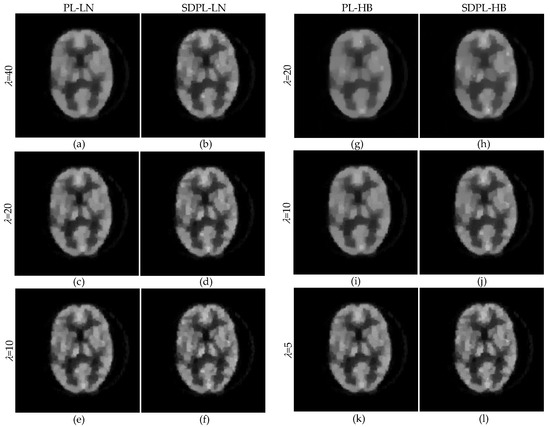

3.1. Numerical Studies Using Digital Phantom

3.2. Qualitative Validation Using Physically Acquired Data